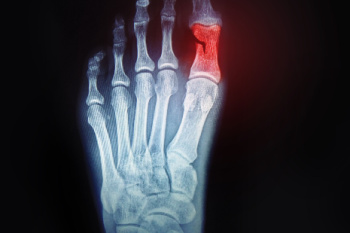

A broken toe is a common injury that occurs when one of the small bones in the foot is fractured due to trauma or excessive force. Causes often include stubbing the toe, dropping a heavy object on the foot, or sports related accidents. Symptoms may involve pain, swelling, bruising, difficulty walking, or visible deformity. Risk factors include participating in high impact activities, wearing improper footwear, osteoporosis, or previous foot injuries. A podiatrist can help by diagnosing the fracture with imaging, providing proper treatment, and guiding recovery to ensure correct healing. If you think you may have broken your toe, do not ignore the pain. It is strongly suggested that you promptly contact a podiatrist who can accurately diagnose and treat this painful condition.

Broken toes may cause a lot of pain and should be treated as soon as possible. If you have any concerns about your feet, contact one of our podiatrists from Arch Foot & Ankle. Our doctors will treat your foot and ankle needs.

What Is a Broken Toe?

A broken toe occurs when one or more of the toe bones of the foot are broken after an injury. Injuries such as stubbing your toe or dropping a heavy object on it may cause a toe fracture.

Symptoms of a Broken Toe

Although the injured toe should be monitored daily, it is especially important to have a podiatrist look at your toe if you have severe symptoms. Some of these symptoms include worsening or new pain that is not relieved with medication, sores, redness, or open wounds near the toe.